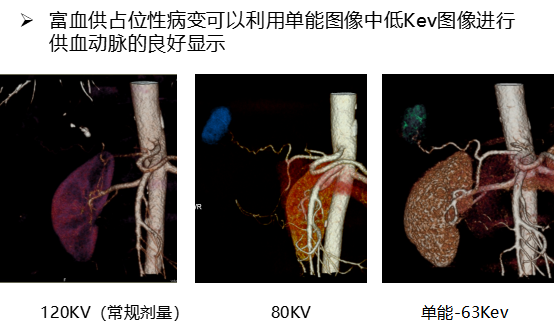

三、能谱单能成像

利用独有的35keV到39kev的低keV图像增加不同组织结构之间的对比 ,有利于等密度病变和小病灶的早期探查、发现,有助于发现乏血供性小肿瘤,显示肿瘤细小供血动脉等 ,可为手术提供依据,如复查栓塞术后效果 ,非常优秀的显示静脉系统,优化动脉成像等。